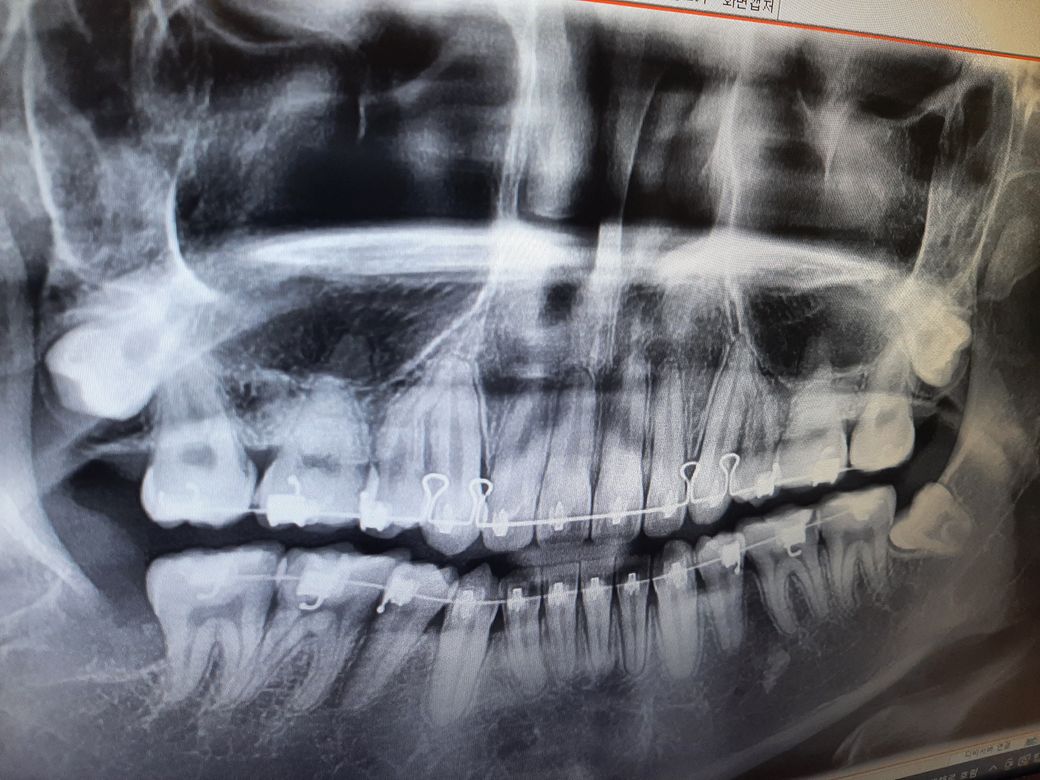

기존교정을 끝냈고 사랑니 발치후 스크류추가교정을 하게되면 치아가 1~2mm정도 뒤로 들어간다는데 입을 들어가게 하고싶어서 하고 싶습니다

아래는 현재상태에요 여기서 1~2mm치아가 들어가면 입이 얼마나 들어갈지요..

그다음 2개는 교정중 1년 8개월 됬을때

다음은 교정후 현재상태에요